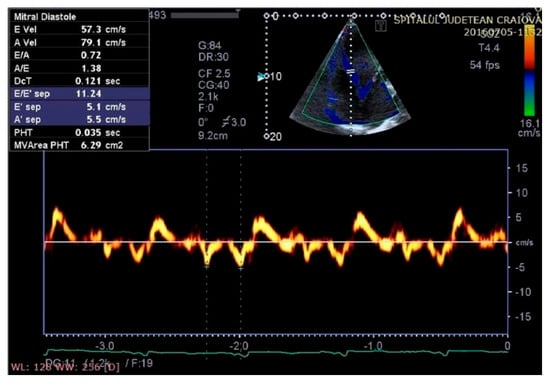

Figure 8.

Aspect of waveforms of tissue Doppler interrogation at the interventricular septum before therapy with a cardiac resynchronization device (yellow color).

Figure 9.

Aspect of waveforms of tissue Doppler interrogation at the interventricular septum after therapy with a cardiac resynchronization device (yellow color).